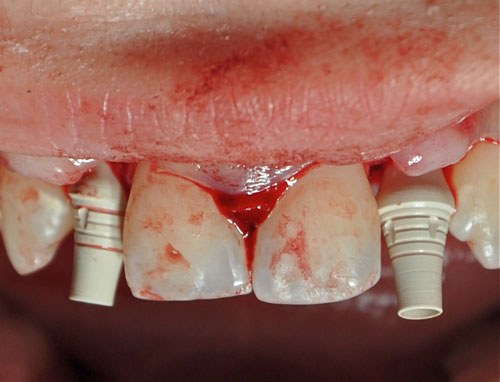

Esto nos obliga a utilizar implantes extremadamente delgados de 2,8 mm por 12mm de la marca BREDENT.

Abordamos con fresa lanceolada para el marcaje del lecho y expandimos con expansores roscados para densificar un hueso de Tipo IV

Instalamos los implantes manualmente y aplicamos dos abuttments temporarios a fin de restaurar en forma inmediata y suturamos.

Realizamos un colgajo vestibular y palatino sin incisión de descarga para preservar lo mas posible el aporte sanguíneo

Instalación de implantes

Instalación de implantes

Instalación de implantes

Instalación de implantes

Implantes instalados

Abbutments temporarios

Tallado de los Abbutments

Sutura